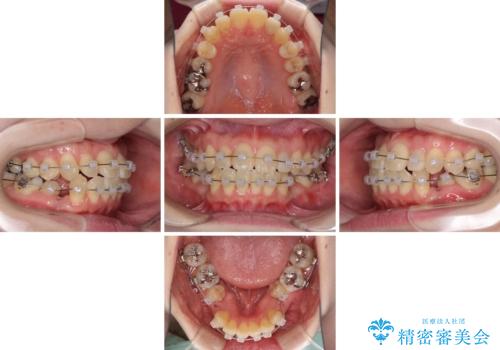

- 矯正装置

- クリアブラケット

- 下顎の歯が舌側に倒れていることと、前歯の咬み合わせの不具合を気にして来院された患者様です。

受け口傾向の口元であるため、下顎左右小臼歯各1歯を抜歯して歯列を整えることとしました。

前歯には治療中の仮歯が装着されていたため、矯正治療後にオールセラミッククラウンにて補綴治療を行うこととしました。

抜歯矯正は2年から2年半程度の治療期間を要することが一般的ですが、僅か1年1ヶ月で終了しました。

あっという間に気になっていた歯並びが改善し、患者様には大変満足していただきました。